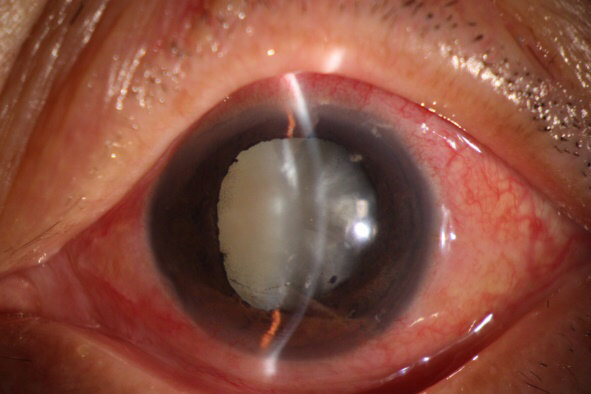

其实病因也基本一样,眼部检查图片如下

这就是典型的白内障未尽早治疗,“長(cháng)得过熟”,而继发青光眼的病例。再追问病史,也都会得到相似的答(dá)案,“早就知道有(yǒu)白内障,都说長(cháng)熟了才能(néng)做”,“電(diàn)视上说有(yǒu)药物(wù)能(néng)控制白内障,能(néng)不做手术就不做吧”等等。